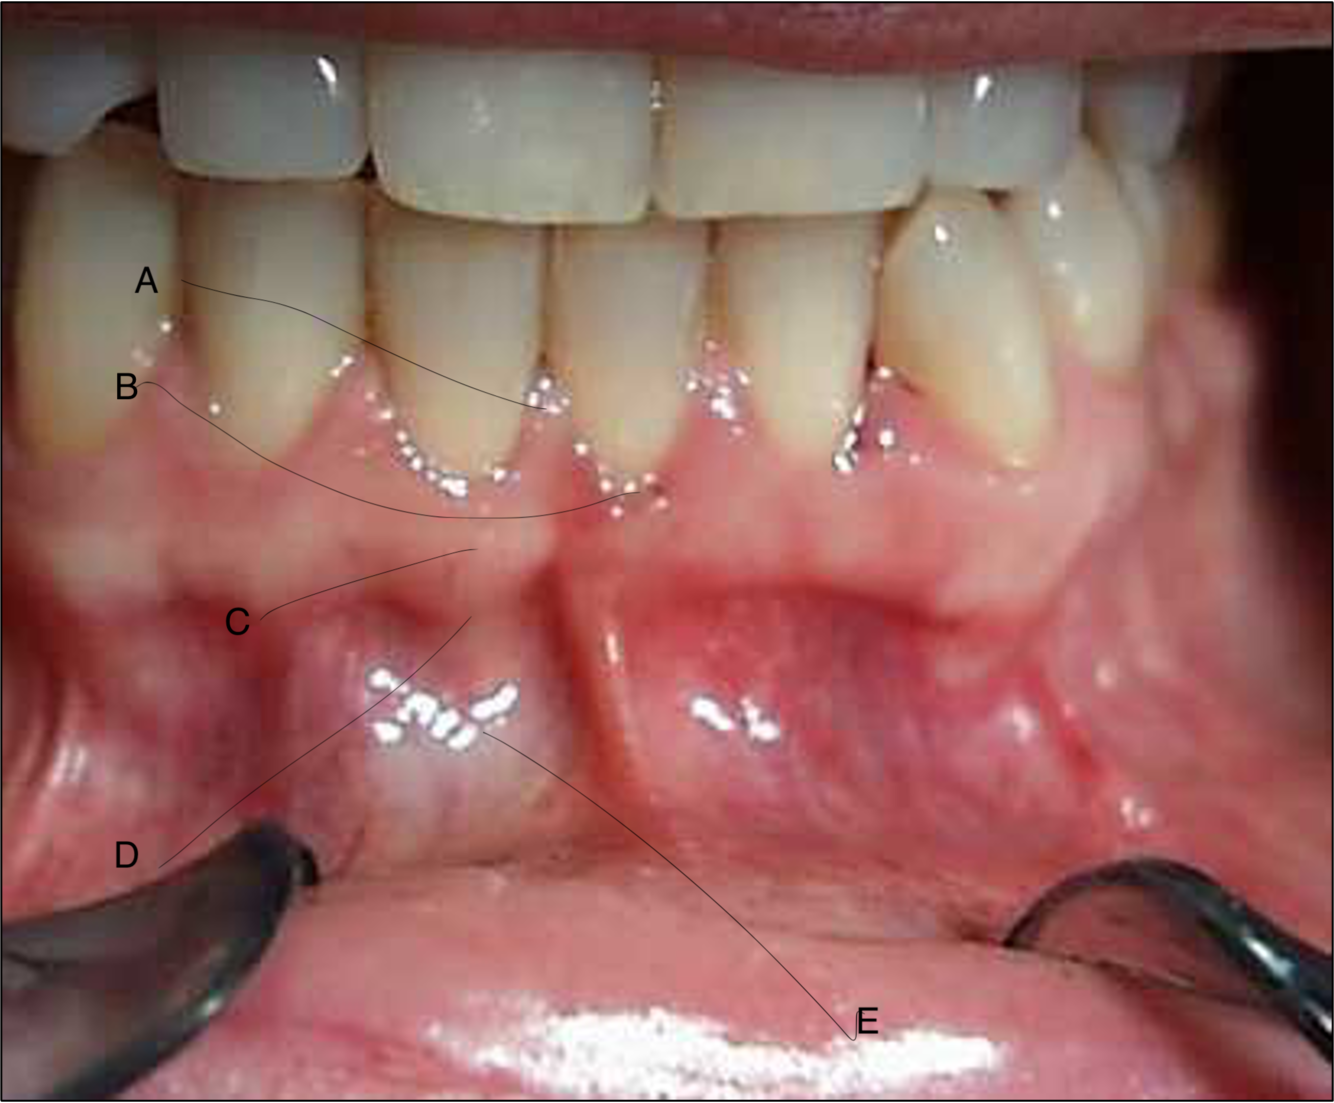

What are the following structures commonly known as?

• interdental papilla

• marginal gingivae

• attached gingivae

• muco-gingival junction

What structure is labelled A on the photo?

interdental papilla

What structure is labelled B on the photo?

marginal gingivae

What structure is labelled C on the photo?

attached gingivae

What structure is labelled D on the photo?

muco-gingival junction

What structure is labelled E on the photo?

oral/alveolar mucosa